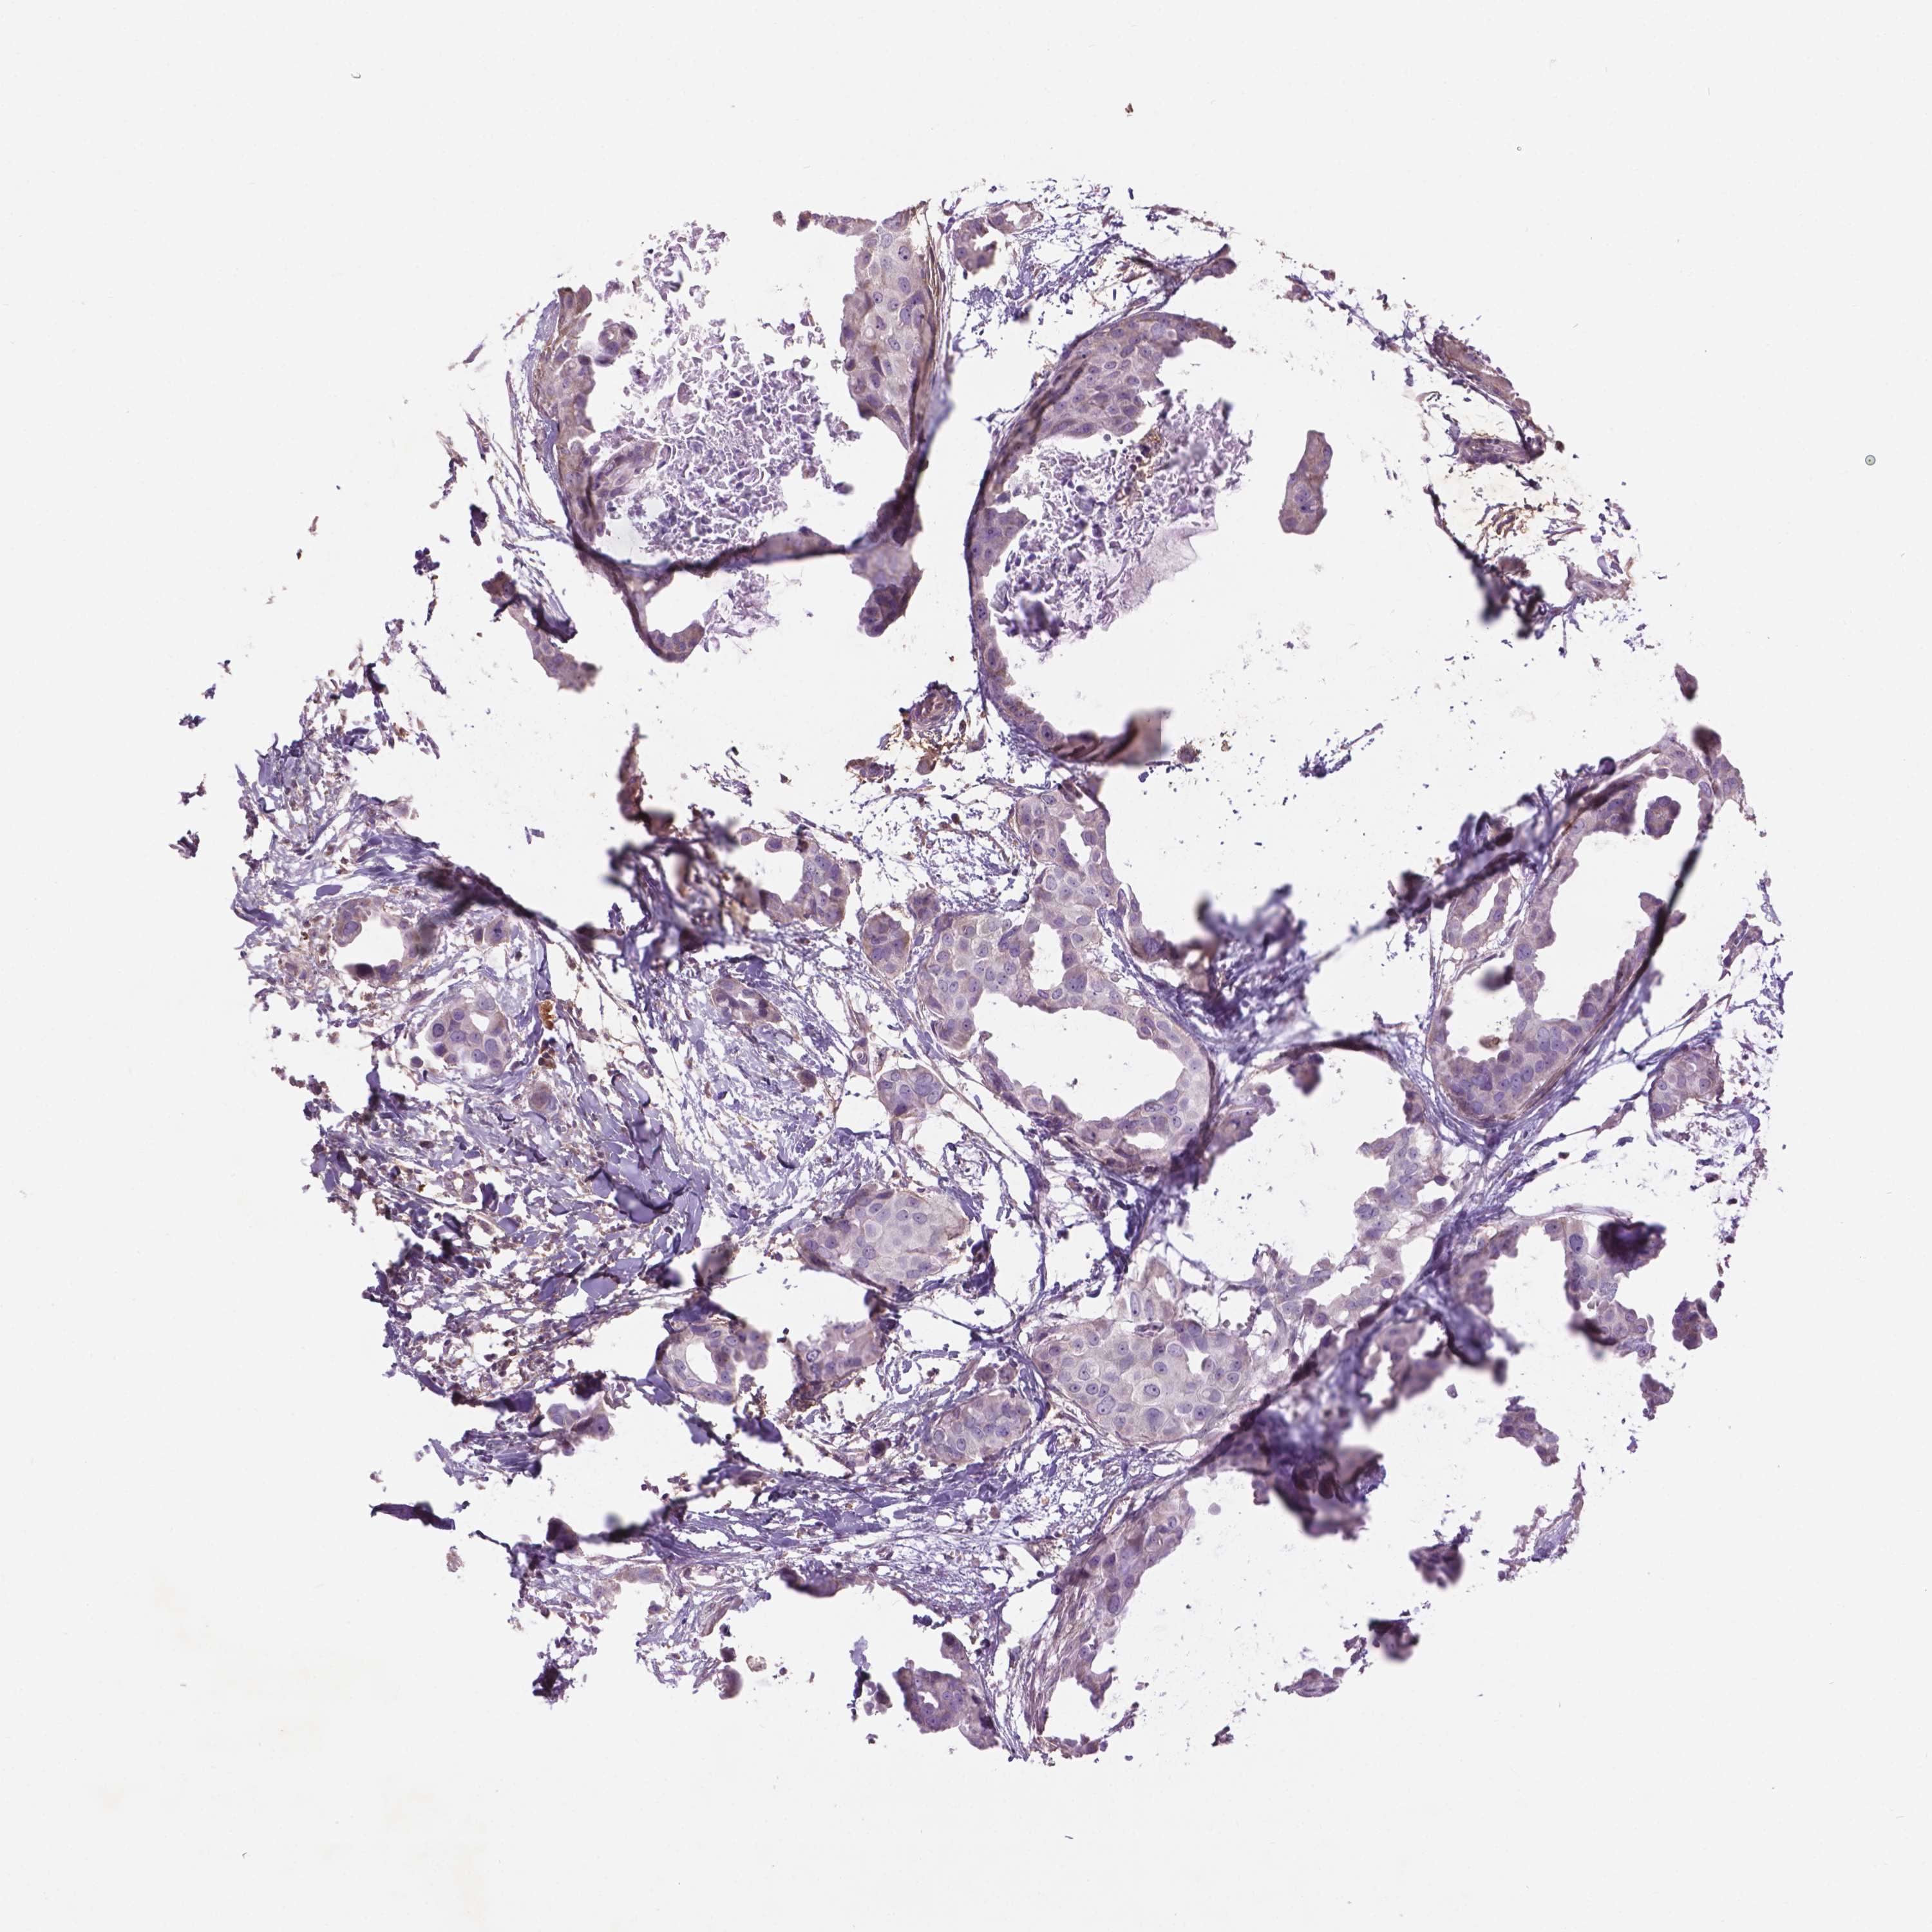

BRCA TCGA BRCA VALIDATION PROTEIN EXPRESSION

ANTIBODIES

AND

VALIDATION